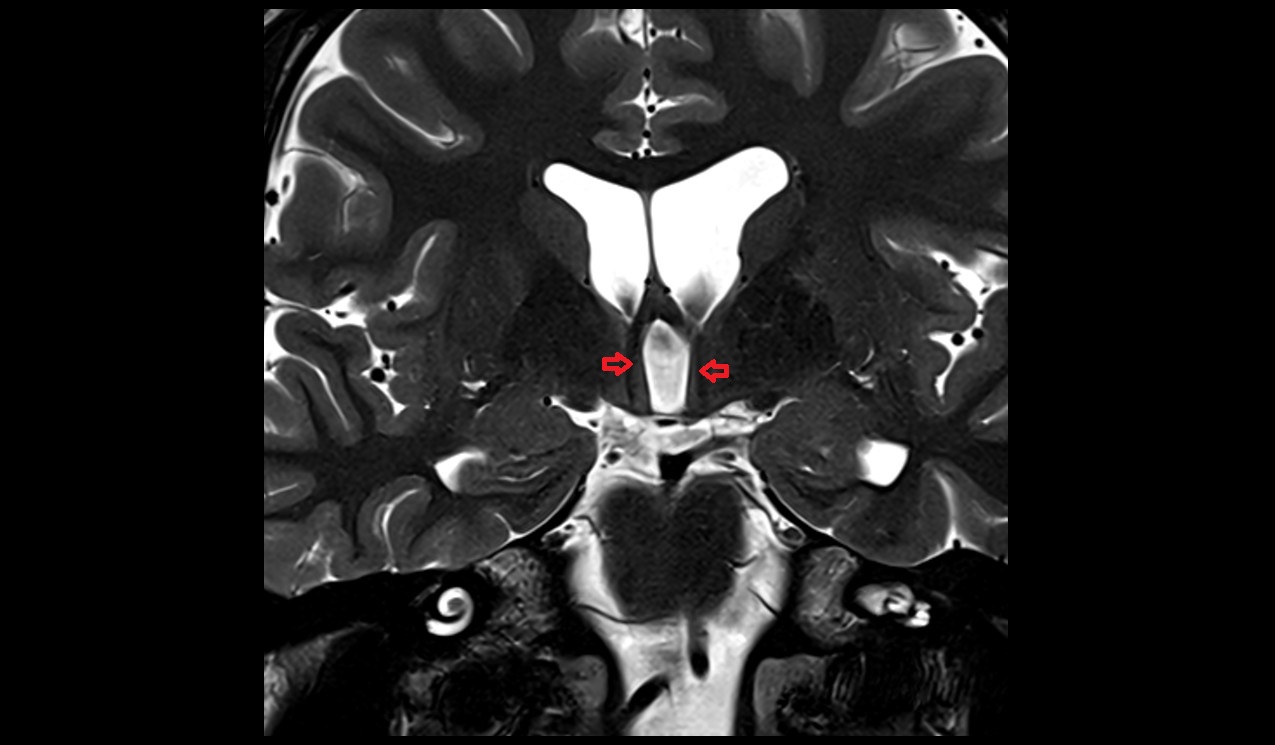

- Interthalamic adhesion